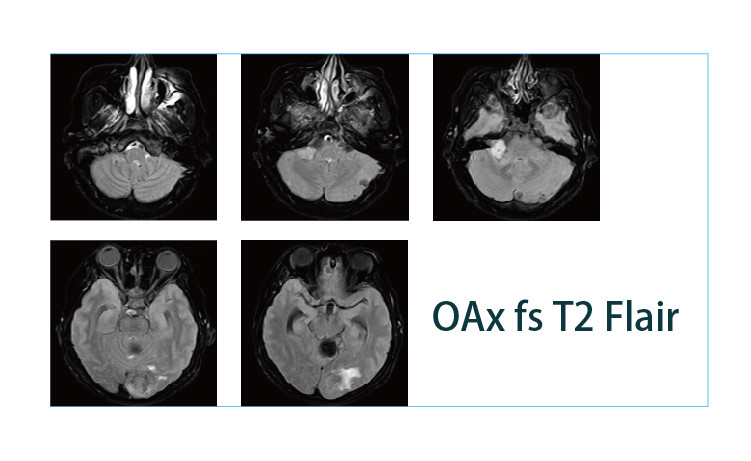

【朗润影像档案】磁共振影像病例分享(编号20190419)